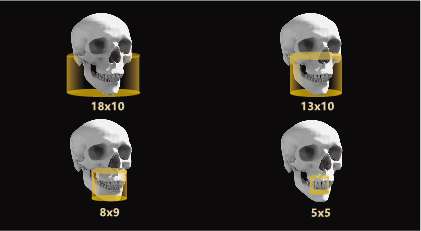

最大视野18X10,多种视野

一个设备含有多种视野,根据患者诊疗需求拍摄不同视野的影像,针对性的选取拍摄面积。